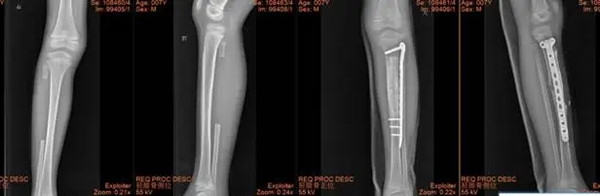

X线可见:长骨骨干处的偏心性、多房性骨质破坏区,边界清楚。

病变区多呈圆形或椭圆形,长轴与骨干平行。

周围可有轻度硬化边,无骨膜反应。

手术方案:左胫骨上段骨肿瘤切除、髓腔刮除植骨、取对侧腓骨植入缺损区,钢板内固定术

手术室内,气氛紧张而凝重,闫主任全神贯注,凭借着高超的医术和丰富的经验,精准地操作着每一个步骤。手术取得了圆满成功,术后的病理结果也再次证实了非骨化性纤维瘤的诊断。